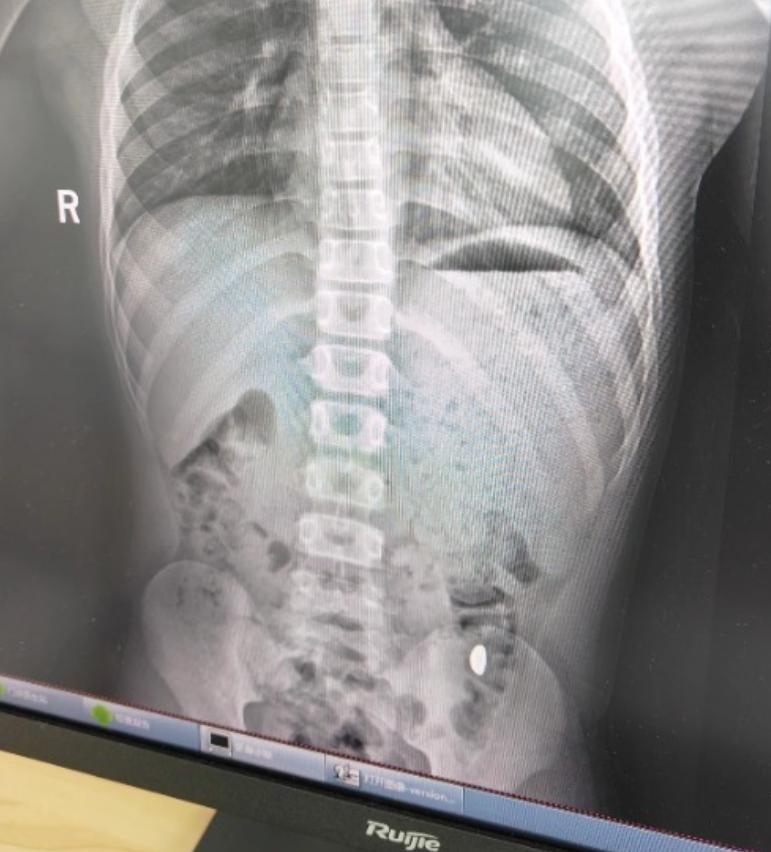

“不作就不会死!”10月27日,江苏昆山,一11岁男孩将妈妈的10克金豆子含在嘴里玩,谁知他一个不小心竟然把金豆吞了下去,妈妈天天嘱咐男孩不要在外面上厕所,网友:在外面如厕的代价有点太大了! 半大男孩正是调皮的时候,他们往往想到什么有趣的事情就会立刻做,根本不考虑后果,一些危险物品照样往嘴里放。 一男孩拿着妈妈万元购入的10克金豆子把玩,他突发奇想,打算用这颗金豆子锻炼自己舌头的力量,于是男孩将金豆含在嘴里转圈。 不料,由于男孩舌头转动速度太快,不慎将金豆顶到了嗓子眼,随后他直接将金豆子吞了下去,这可把男孩吓了一跳,他想到电视剧里一些“吞进自杀”的情节,哭着跑去告诉妈妈自己吃了金豆子,可能要“死”了。 妈妈一开始还以为男孩在开玩笑,没想到竟然是真的,她十分无奈,打算让男孩自行排出,害怕金豆遗落在外,还天天嘱咐孩子不能在外面如厕。 五天之后,男孩还是没有排出金豆,妈妈带他来到了医院,好在当天下午金豆子被顺利排出,男孩的身体也无大碍。 不少网友表示,男孩这要是在外面如厕时排出金豆子,这个代价未免也有点太大了,贵重物品一定要妥善保管,也要提醒孩子不要做出危险的行为! 信息来源:《11岁男孩误吞10克金豆,妈妈:天天叮嘱他不要在外面大便》大象新闻